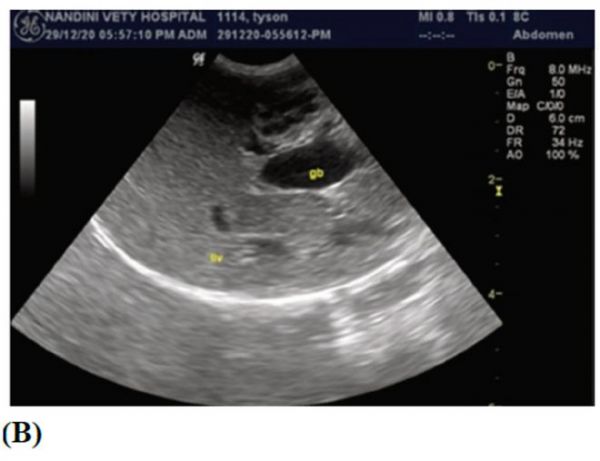

• 猫的胆囊可呈双叶状。胆囊和胆管可见至大十二指肠乳头水平。正常情况下胆囊内容物无回声(图1B)。

图1 犬(A)和猫(B)的肝脏超声对比图。犬的胆囊内容物有轻微回声(A);而猫的胆囊内容物没有回声(B)。